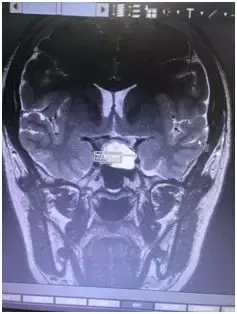

垂体磁共振结果显示,小陈的垂体上有一个大约2.3cm*1.9cm*1.6cm瘤体。

这个小小的瘤就是引起她闭经、泌乳的罪魁祸首。

垂体冠状位图见泌乳素瘤